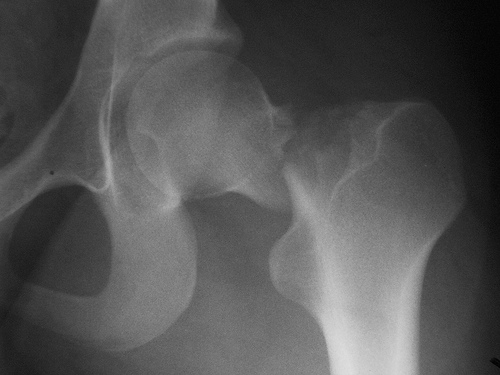

Fármacos y fracturas en los ancianos

Un estudio halló que más del 75% de los pacientes fracturados recibían fármacos que aumentan el riesgo de fractura. Además, la mayoría los siguió utilizando después. JAMA Internal Medicine, 22 de agosto de 2016